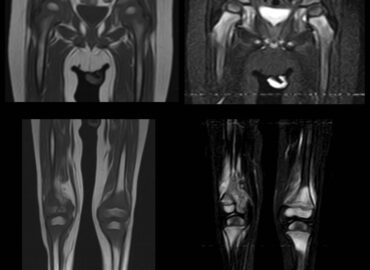

4 años de edad. Dolor de MMII y cojera de 3 meses de evolución, asociado a episodios IRA y […]